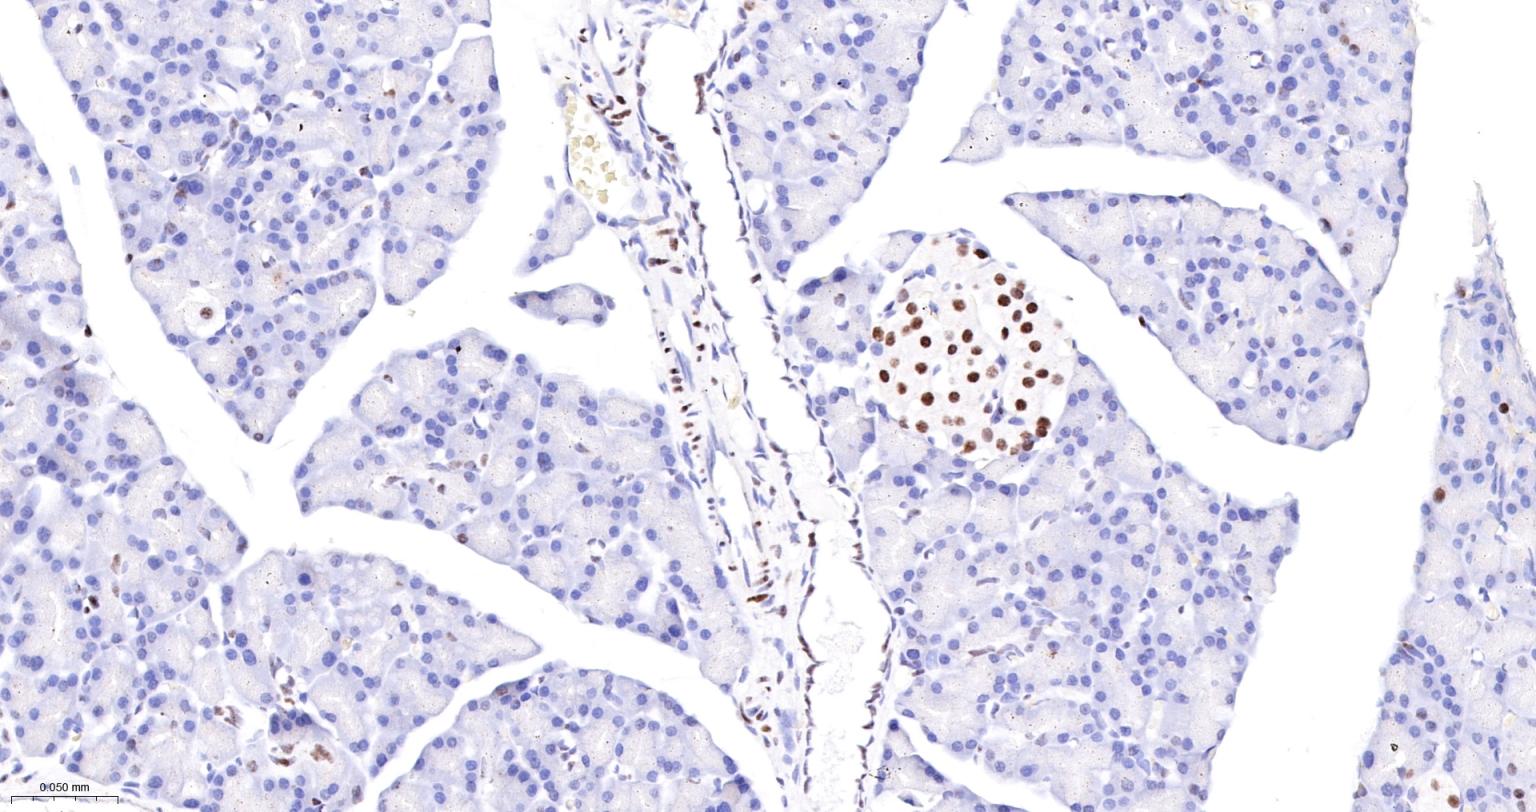

Paraformaldehyde-fixed, paraffin embedded Rat Pancreas; Antigen retrieval by boiling in sodium citrate buffer (pH6.0) for 15 min; The section was incubated with FUBP1 Monoclonal Antibody, Unconjugated (bsm-60625R) at 1:200 overnight at 4°C, followed by conjugation to the bs-0295G-HRP and DAB (C-0010) staining.

Paraformaldehyde-fixed, paraffin embedded Mouse Pancreas; Antigen retrieval by boiling in sodium citrate buffer (pH6.0) for 15 min; The section was incubated with FUBP1 Monoclonal Antibody, Unconjugated (bsm-60625R) at 1:200 overnight at 4°C, followed by conjugation to the bs-0295G-HRP and DAB (C-0010) staining.